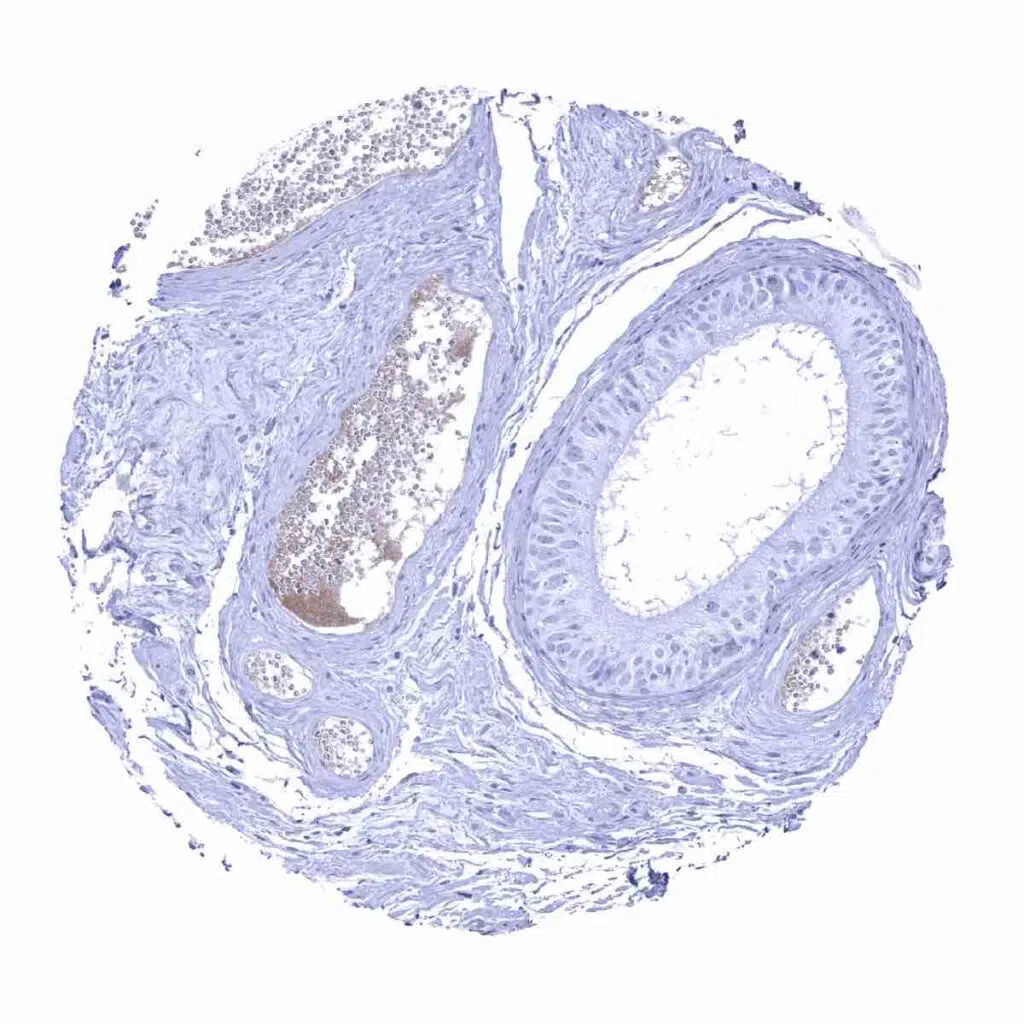

Epididymis – Rabbit anti-human IgA positive plasma cells are lacking in the epididymis but some Rabbit anti-human IgA staining occurs in blood serum.